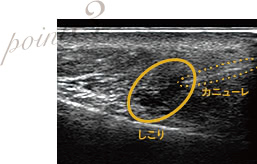

しこり除去の際はエコーを使用

しこりはヒアルロン酸溶解注射・ヒアルロニダーゼで溶かします。しこりの除去には必ずエコーを使用し、しこりに的確に注射を行います。小さいしこりの場合は、溶解されれば自然と吸収されますが、当院では本当に吸収されたか、後日エコー検査で確認を行い、術後の仕上がりとゲストの健康状態に責任を持ちます。